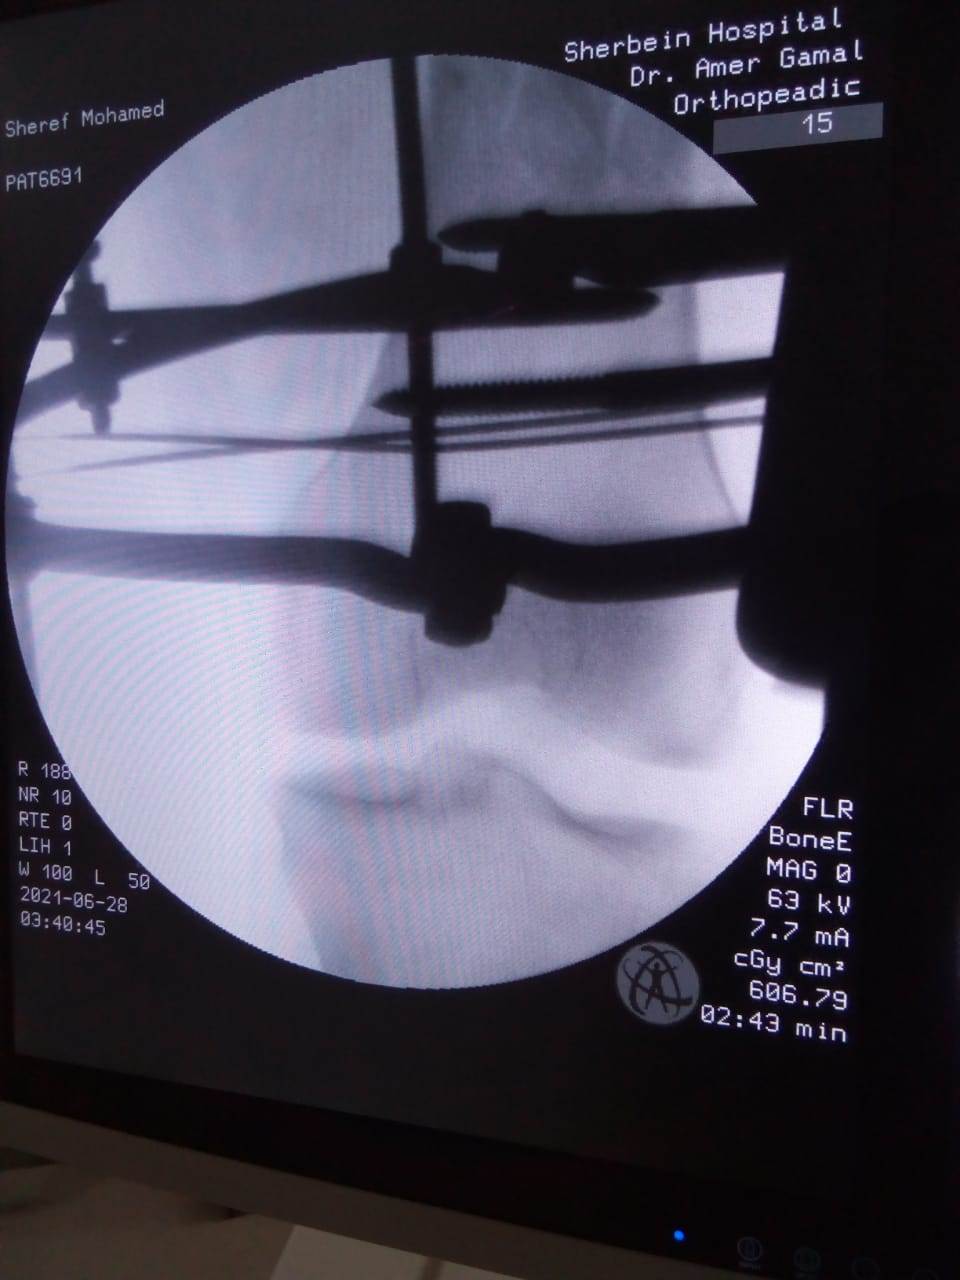

حيث تم إجراء تدخل جراحي دقيق لشاب يعاني من كسر مضاعف من الدرجة الثالثة، إثر طلق ناري، أدى إلى تهتك بالأنسجة، وكسور متفتتة بالفخذ، وذلك عن طريق جهاز "الليزاروف"، وتعد واحدة من عمليات العظام الكبرى والمتقدمة ذات المهارة الخاصة.